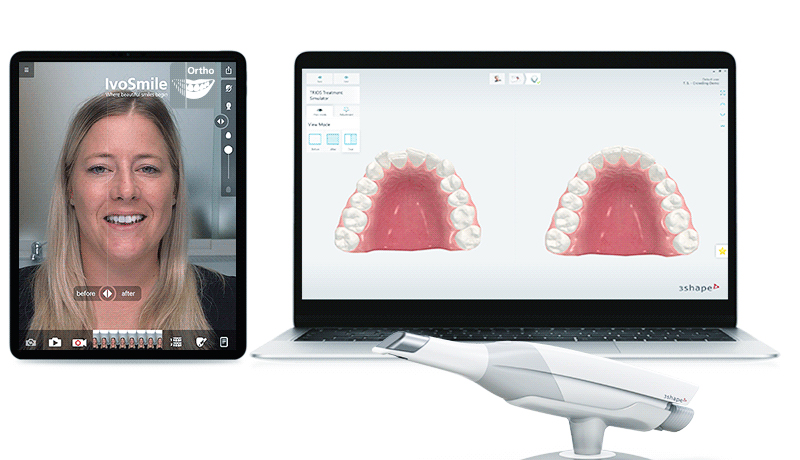

完成的影像数据、及三维数据模型,经数据云传输至MAC数字化精确方案设计中心,通过AI人工智能软件、循证医学病例数据库,融入咬合关系、基台牙冠等修复信息,完成咬合关系重建、模拟种牙理想路径,实现“以修复为导向”的种植方案设计。

种植牙修复,除了功能还兼顾美学,基于以修复为导向的核心理念,麦芽口腔MAC种牙方案设计,不仅能找到理想的植入路径,还能针对独立个体,设计符合红白美学、颜面美学、生物力学、以及组织生物学的个性化基台与义齿修复冠,迷人笑容触手可得。

定制黄金笑曲,科技提升颜值

依托智能方案设计,麦芽口腔实现将图片数据转化为三维模型,11项微笑数据的定制,让您拥有自然健康、整齐亮白的笑容。